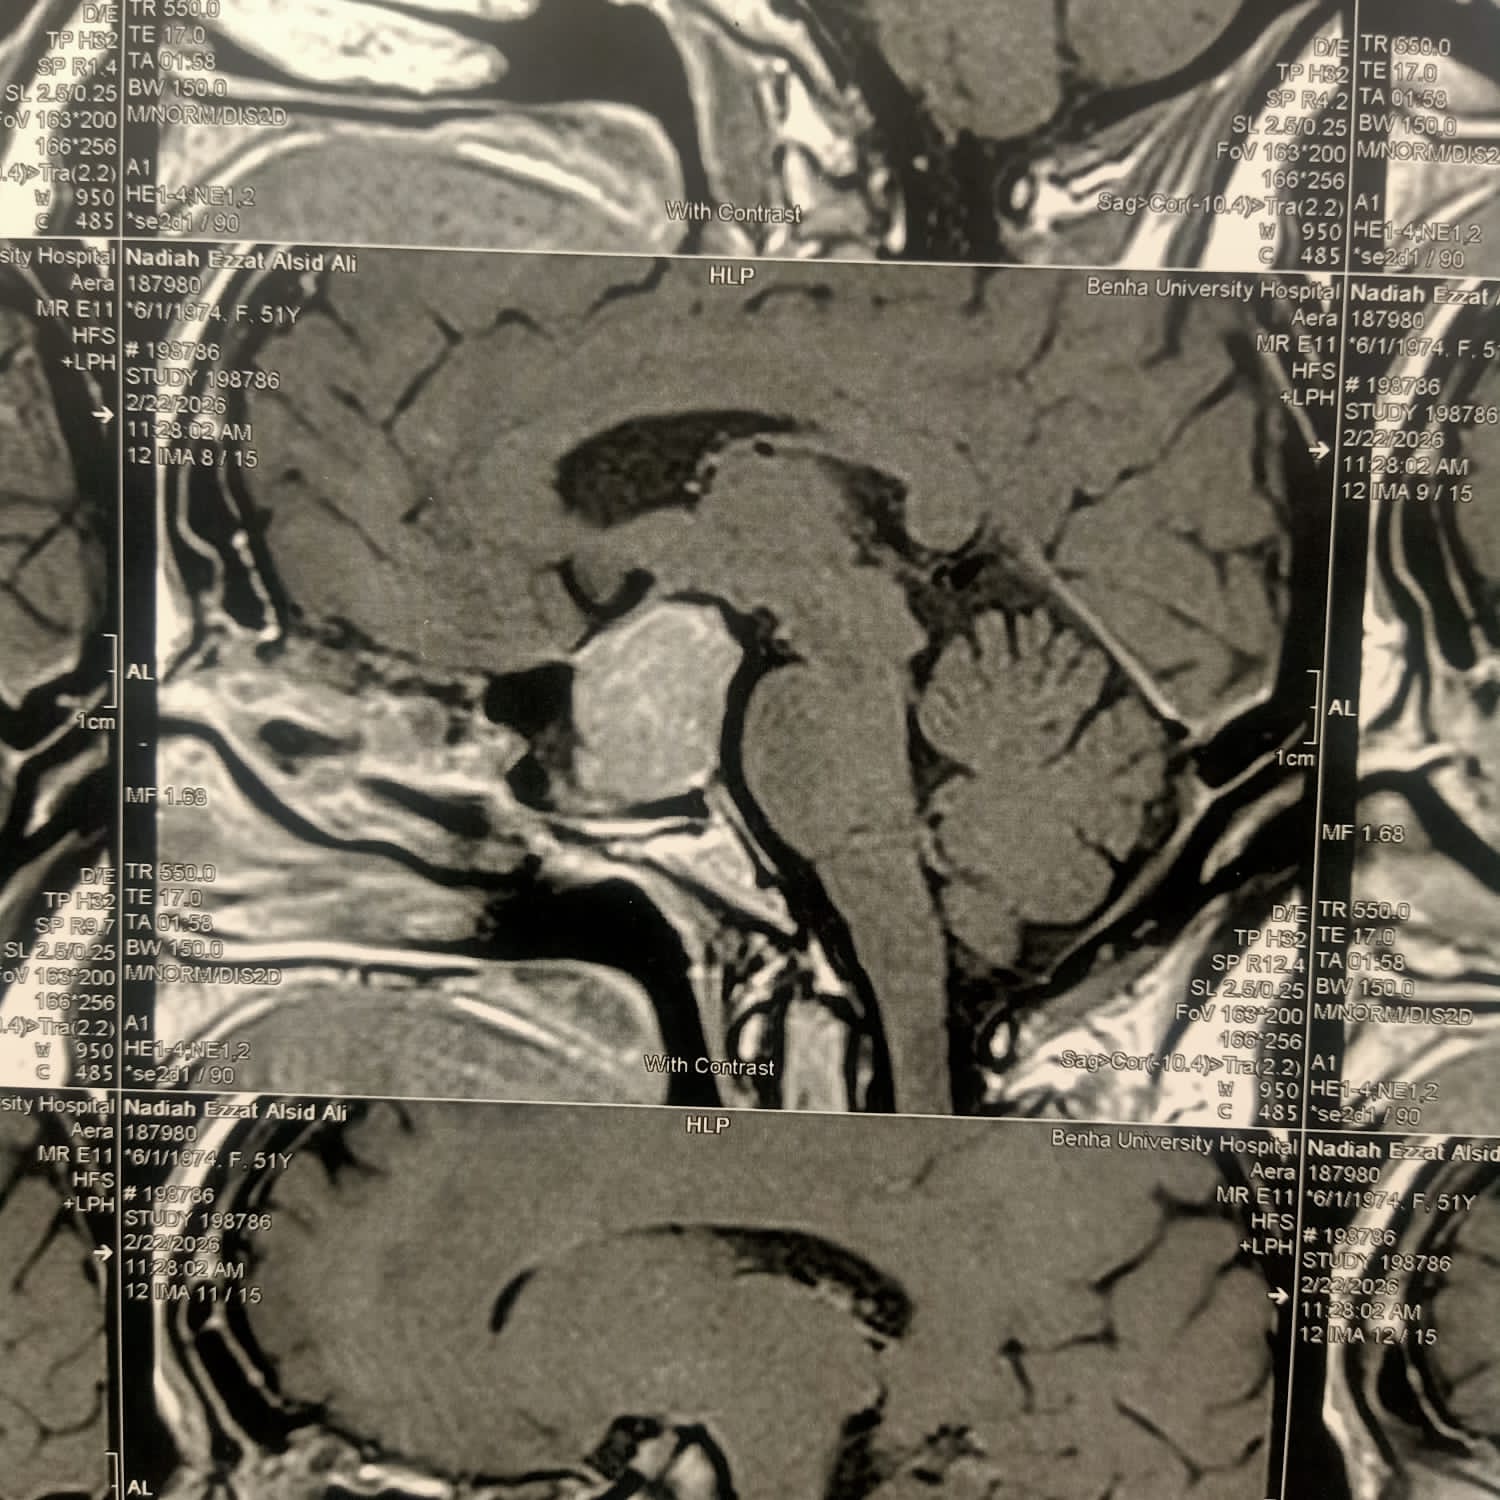

نجح فريق طبي بمستشفيات جامعة بنها في إجراء جراحة دقيقة ومتقدمة لاستئصال ورم ضخم بالغدة النخامية في قاع الجمجمة لمريضة تبلغ من العمر 52 عامًا، كانت مهددة بفقدان بصرها، وذلك باستخدام منظار الجيوب الأنفية دون الحاجة إلى فتح جراحي بالجمجمة.

وكانت المريضة تعاني من ضعف شديد في الإبصار، وصداع مستمر، إلى جانب اضطرابات هرمونية، حيث كشفت الفحوصات الطبية عن وجود ورم بالغدة النخامية يضغط بشكل مباشر على العصب البصري.

وتمكن الفريق الطبي من استئصال الورم بالكامل باستخدام المنظار عبر الجيوب الأنفية، في جراحة مشتركة بين قسمي جراحة المخ والأعصاب والأنف والأذن والحنجرة، دون إجراء أي فتح جراحي خارجي للجمجمة.

وأكدت إدارة المستشفيات أن الحالة الصحية للمريضة مستقرة تمامًا وبوعي كامل، وتخضع حاليًا للمتابعة الطبية الدقيقة بعد التأكد من الاستئصال الكامل للورم من خلال الأشعة المقطعية، تمهيدًا لخروجها من المستشفى خلال الفترة المقبلة.